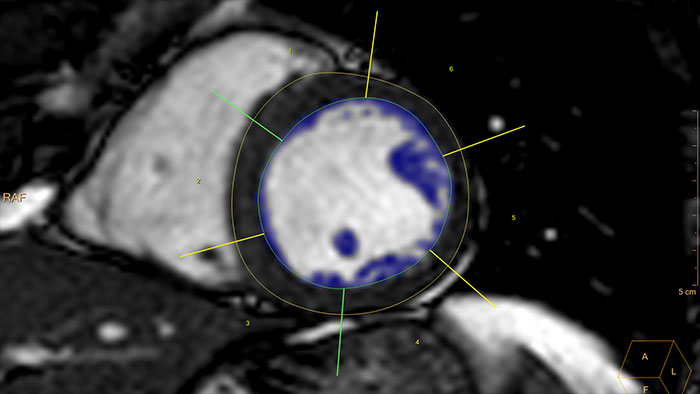

- Cardiac

-

MR Cardiac

Detailed quantification of cardiac function

Includes a viewer and functional analysis. The MR Cardiac Viewer allows side-by-side review of single, multiple or all available cardiac series in a default or in a user-defined viewing protocol. It automatically links multiple series in respect to DICOM geometry, zoom/pan, time and position link for qualitative assessment and analysis in AHA 17 segment templates of the MRC data types. It supports basic measurements and screen captures.

Benefits

- The application provides semi-automatic and manual tools for segmentation.

- Results are calculated based on the Simpson method. The user has an option to apply automatic papillary muscles extraction if desired.

- Results tables can be configured by the user, and values indexed by Body Surface Area (BSA).

- RV segmentation workflow is simplified to be harmonized with LV, and enhance visibility of the phase-prorogation capability.

- Left ventricle volumetric analysis based on single or multi-slice, multi-phase or real-time dynamic 2 Chambers and/or 4 Chambers long axis image acquisitions is also supported based on the Area Length Ejection Fraction (ALEF) single or bi-planar method.

- All results and screen captures can be collected, saved and exported by the user in a Findings Navigator functionality.